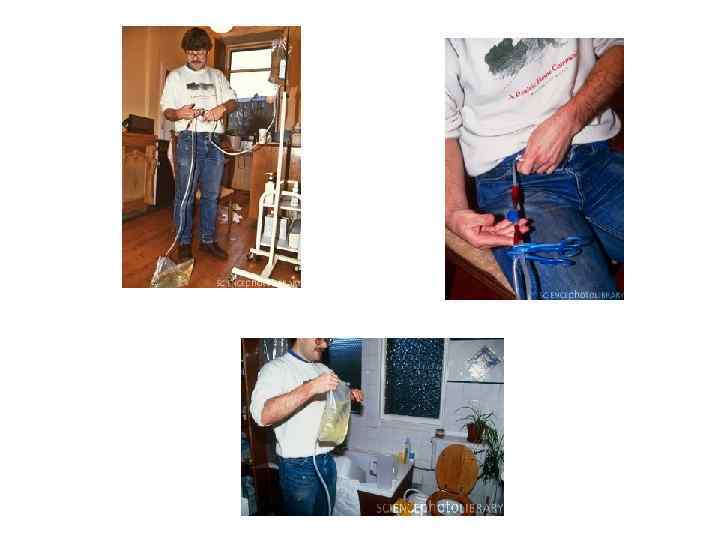

заместительное лечение почечной недостаточности Когда наступает 5 -я стадия ХБП (СКФ <15 мл/мин. ) — почечная недостаточность, назначают заместительное лечение. В настоящее время существуют три метода заместительной терапии: гемодиализ, перитонеальный диализ и трансплантация почки.

заместительное лечение почечной недостаточности Когда наступает 5 -я стадия ХБП (СКФ <15 мл/мин. ) — почечная недостаточность, назначают заместительное лечение. В настоящее время существуют три метода заместительной терапии: гемодиализ, перитонеальный диализ и трансплантация почки.